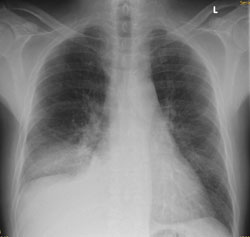

Ein 68-jähriger Patient mit chronischer Niereninsuffizienz und hypertensiver Herzerkrankung klagt akutell über zunehmende Dyspnoe. Sie veranlassen ein Thoraxröntgen.

Thorax seitlich

Bild vergrössern

Welcher Befund liegt vor? (mehrere richtige Antworten möglich)